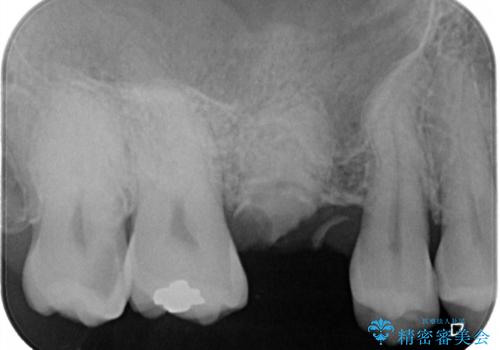

強い痛みのあった歯は、既に神経組織が失活しており根管治療が必要でした。

反対側の歯は、歯根だけが歯肉に埋もれて残っている状態のため、抜歯が必要な状態でした。

歯根だけとなっている歯はインプラントに、神経組織の失活している歯は根管治療を行い、いずれもオールセラミッククラウンにて補綴治療を行うこととしました。